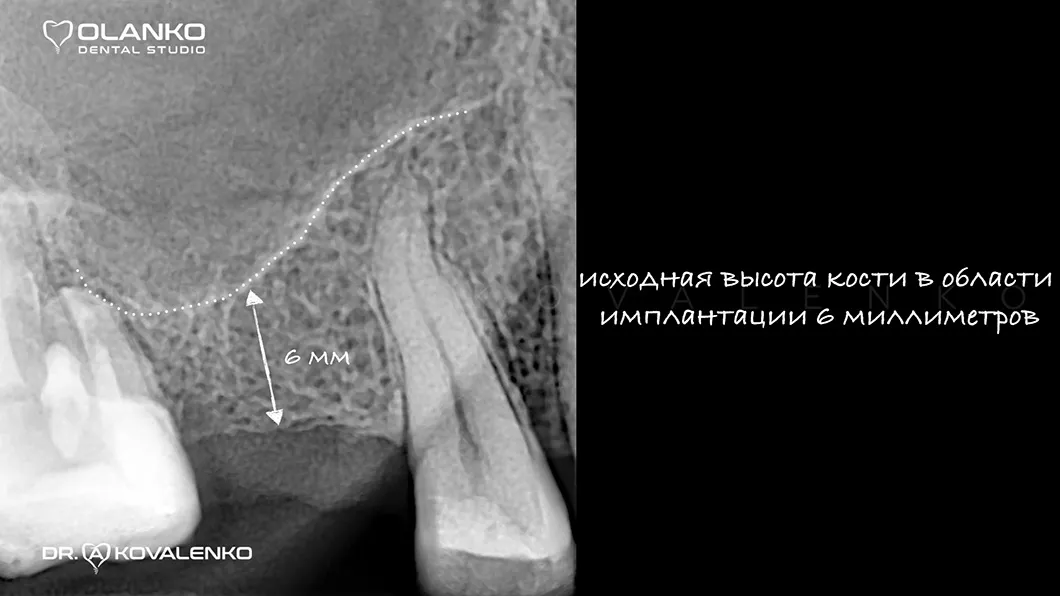

Специалисты Olanko dental studio (Оланко) г. Бровары рекомендуют проводить операцию по установке зубного имплантата в максимально ранний период после удаления проблемного зуба (от 3 до 6 месяцев), или использовать методику имплантации одномоментно с удалением зуба тогда, когда есть условия для проведения такой операции. Но если убыль костной ткани уже наступила, мы прибегаем к использованию хирургического восстановления объёмов костной ткани — костной пластике.

Костная пластика – это хирургическая операция, которая позволяет восстановить объём челюстной кости, для будущей зубной имплантации, с помощью костной ткани, взятой в донорских зонах у пациента, или искусственного костнопластического материала, а также смеси костных материалов.

Операция костной пластики может выполнятся как самостоятельно, так и совместно с установкой зубного имплантата.

Специалисты Olanko dental studio (Оланко) г. Бровары, при выборе метода костной пластики, проводят детальный анализ компьютерной томографии и виртуально расставляют положение будущих имплантатов в специальном программном обеспечении IMPLANT STUDIO 3Shape.